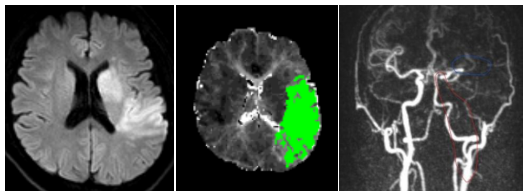

綜合《揚子晚報》等內地媒體報道,35歲王先生因突然出現了口角歪斜、言語不能、右側偏癱等癥狀,隨即報警,被送到南京市第一醫院就醫,確診急性缺血性腦梗死,原因是王先生腦內左側頸動脈和左側大腦中動脈發生了堵塞。

接診的侯建康醫生指出,頸動脈位置表淺,如果持續受外力刺激及損傷,如頸部按摩、快速劇烈轉頸、舉重、瑜伽等,在特定情況下有可能形成動脈夾層。王先生的頸動脈夾層大概率是因為使用按摩槍按摩頸部過猛、過頻所致。侯醫生提醒,頸部按摩一定要謹慎,切忌用力過猛、頻率過高。慶幸王先生在手術後已康復出院